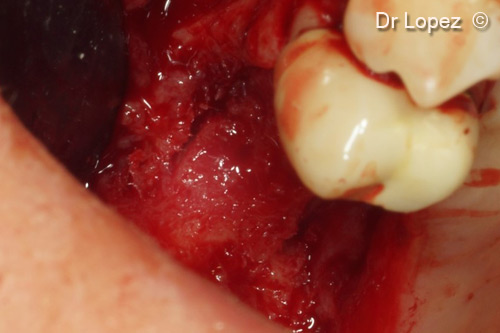

5. Two bone slots of 2 mm depth prepared on vestibular and palatine sides ready to receive Curved Lamina®

6. Curved Lamina® stabilized by the two slots and containing mixed graft of GTO® and scraped bone in ratio 50%